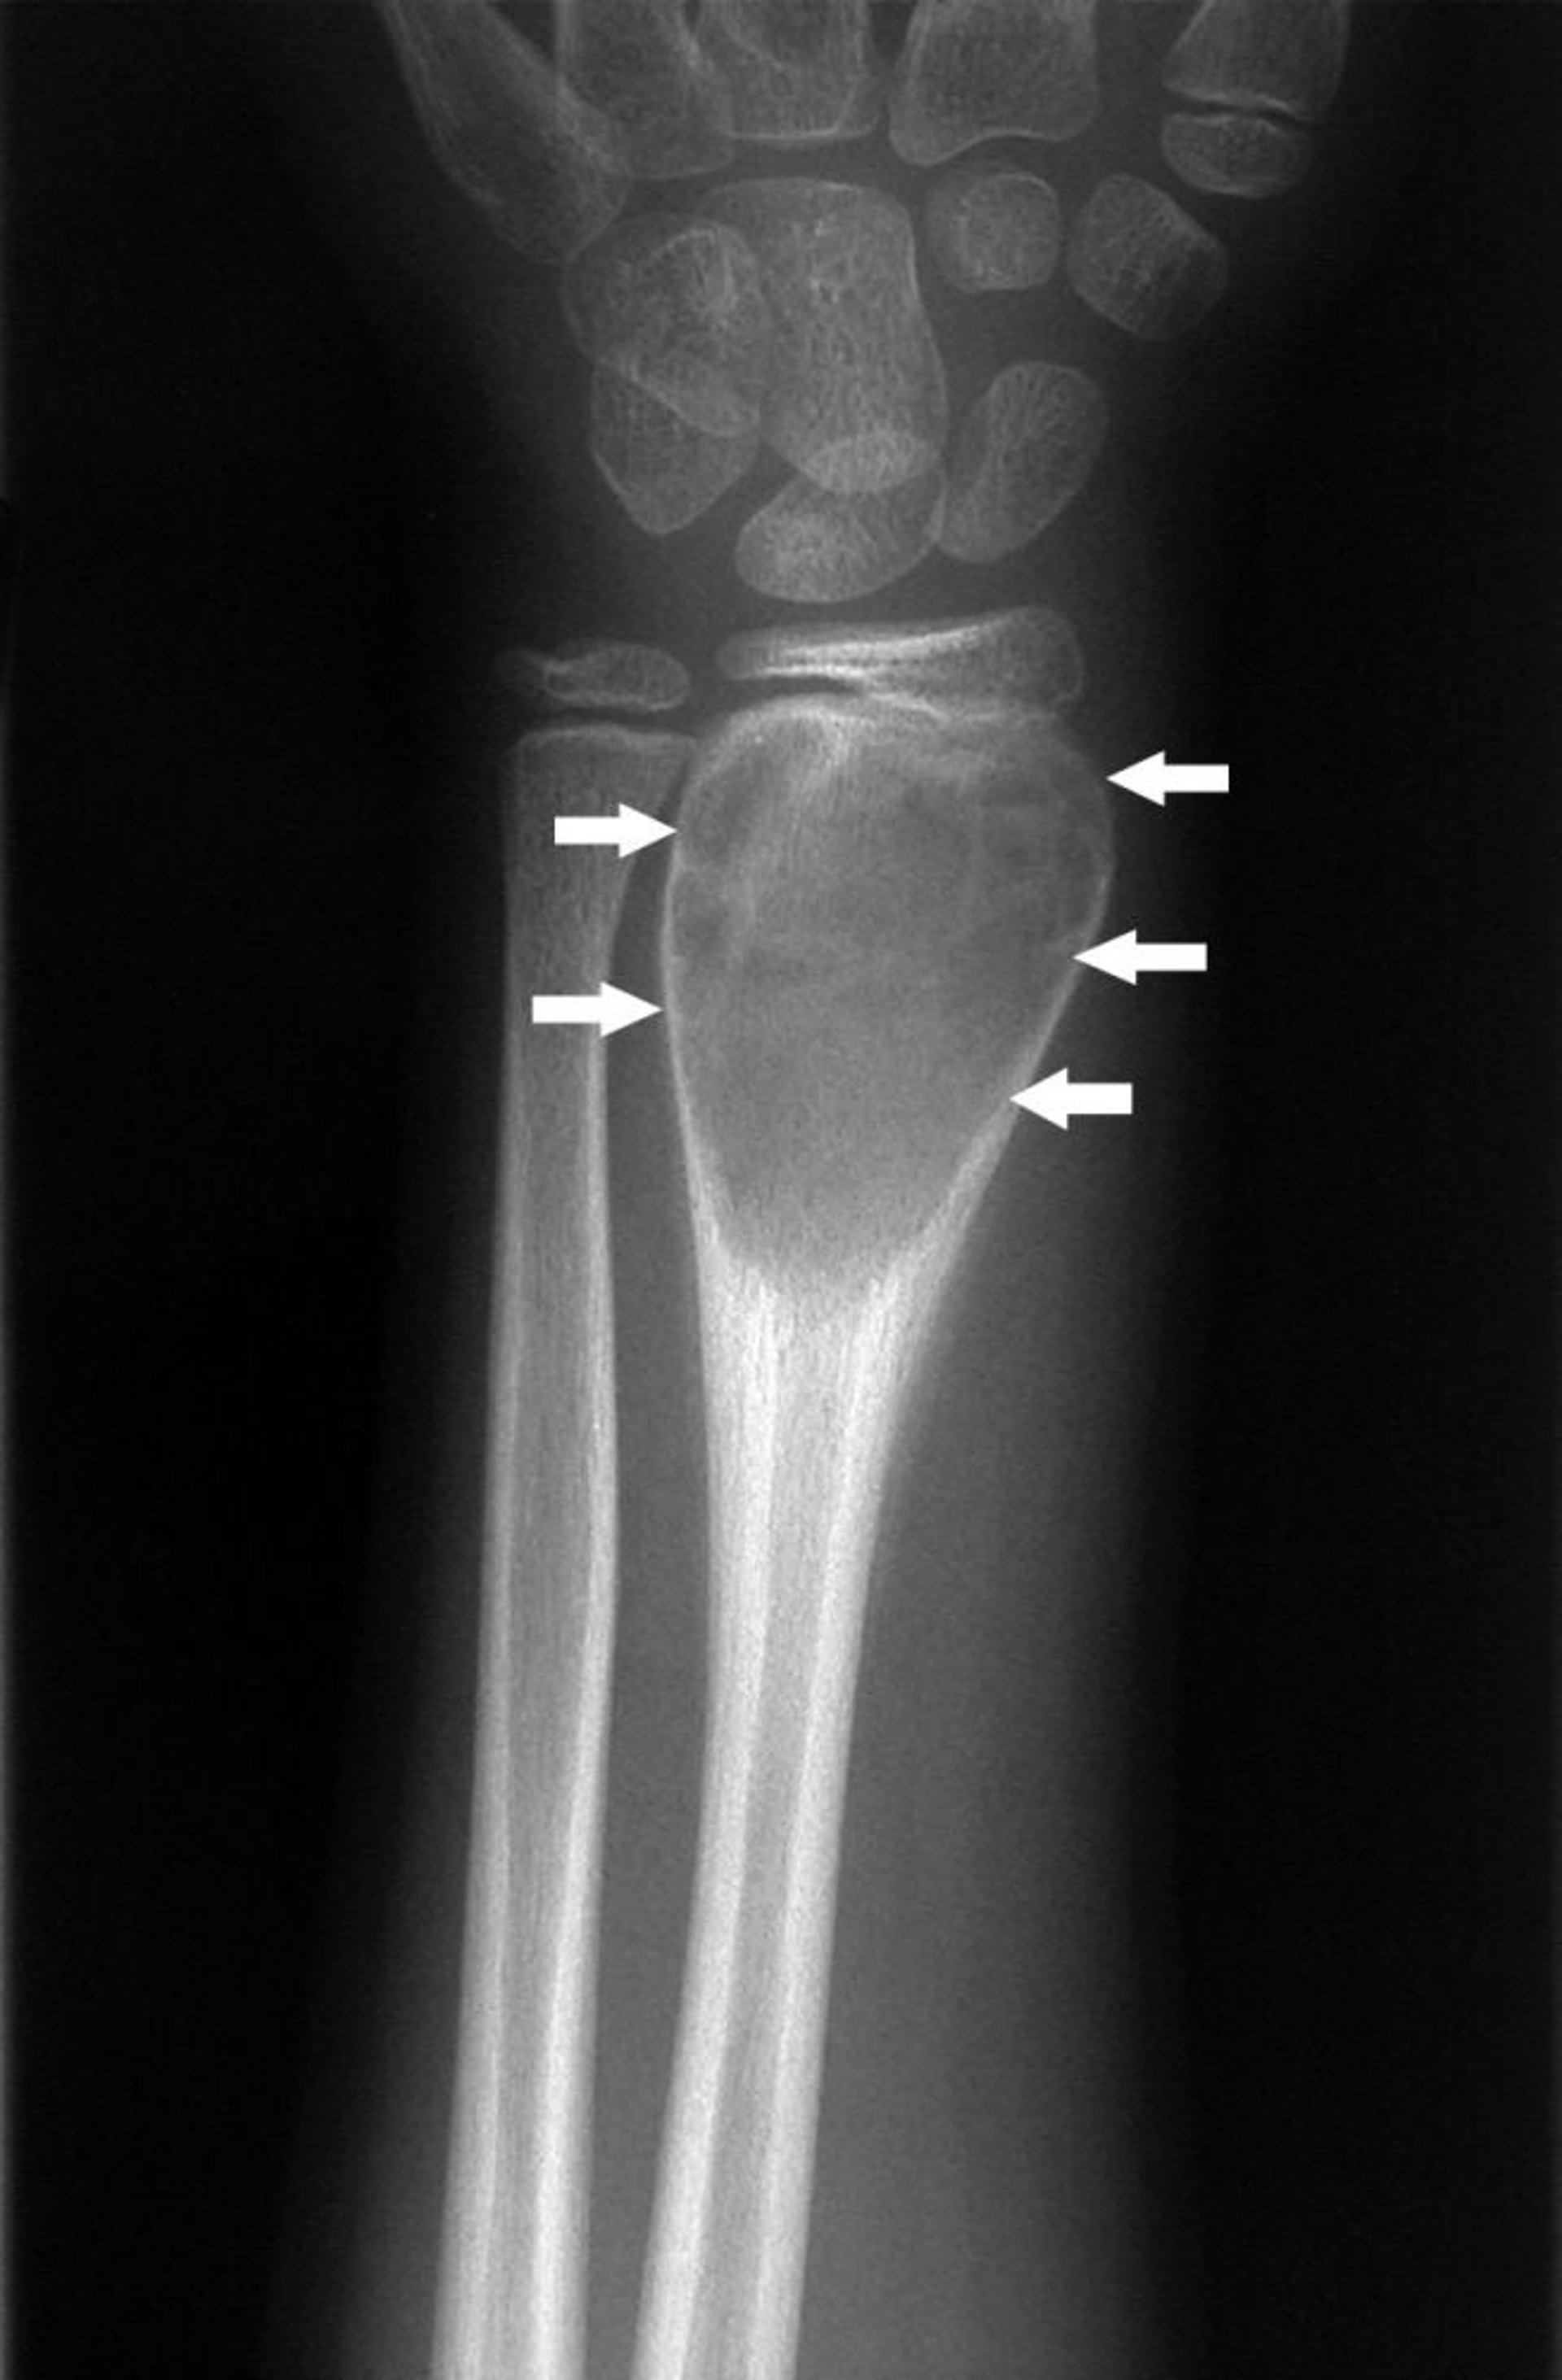

Nang xương phình mạch ở cổ tay

Phim chụp X-quang cổ tay này cho thấy hình thành xương mới ở màng xương xung quanh tổn thương mở rộng (mũi tên), đặc trưng của u nang xương phình mạch.

Hình ảnh do bác sĩ Michael J. Joyce, và bác sĩ Hakan Ilaslan cung cấp.